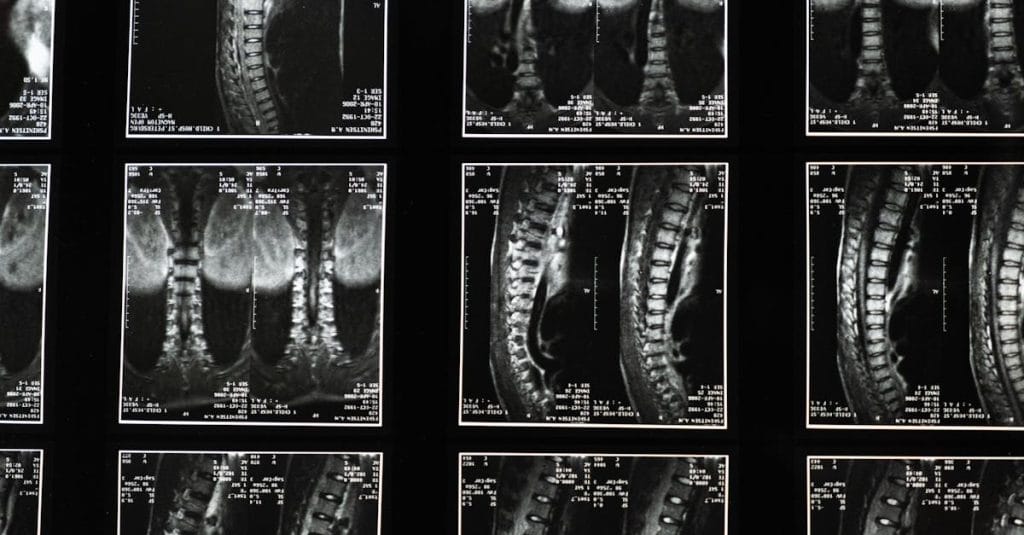

Quels examens sont nécessaires avant de commencer un traitement de décompression pour la sciatique?

Une IRM ou une radiographie est généralement recommandée pour évaluer l’état de la colonne vertébrale.

Quels examens permettent de diagnostiquer la sciatique?

Une IRM ou une radiographie est généralement nécessaire pour confirmer la cause de la sciatique.